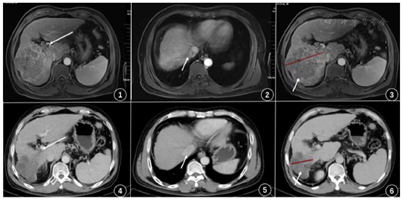

2020年12月11日复查胸部CT示:左肺小结节,转移可能。2021年7月13日复查胸部CT示:左肺下叶结节,呈治疗后改变,较前增大。2021年9月10日复查上腹部MRI示:肝右叶异常信号,考虑子灶。

患者入院完善检查后,于2020年3月8日行肝穿刺活检,病理诊断回示:(肝穿刺)癌组织,倾向肝细胞癌。经多学科讨论,考虑患者无手术机会,建议行卡瑞利珠单抗免疫治疗联合阿帕替尼靶向治疗。经患者同意于2020年3月13日开始口服甲磺酸阿帕替尼(500 mg/d)靶向治疗联合静脉输注PD-1抗体卡瑞利珠单抗(200 mg/3周)免疫治疗及长期口服恩替卡韦片(0.5 mg/d)抗病毒治疗。患者用药后无明显原因出现发热,最高体温达38.0℃,行胸部CT及多次血培养检查未提示与感染相关,考虑与用药后肿瘤坏死引起无菌性炎症相关,给予对症治疗后较前好转。复查患者血常规及肝功能提示血小板、白细胞持续降低及转氨酶、总胆红素持续升高,血小板22×109/L,白细胞1.42×109/L,总胆红37.6 umol/L,谷草转氨酶341 U/L,给予对症治疗未见好转,根据NCI-CTCAE4.03标准,考虑出现应用靶向药物不良反应—严重骨髓抑制(3级)及肝功能损伤(3级),于2020年3月31日给予停用甲磺酸阿帕替尼,加用长期皮内注射胸腺肽(1.6 mg,2次/周)提高免疫力后上述症状较前好转。上述治疗方案治疗2个周期后复查腹部增强CT提示肝右叶占位及静脉癌栓较前缩小,甲胎蛋白降至788.0 ng/ml。患者头部皮肤出现少量皮疹,根据《CSCO免疫检查点抑制剂毒性管理指南》及NCI-CTCAE4.03标准,考虑患者出现与PD-1抗体治疗相关不良事件-反应性皮肤毛细血管增生症(1级),给予局部使用润肤剂后可耐受,未停药。治疗4周期后行腹部增强CT提示肝右叶占位较前范围缩小(图6),门脉主干癌栓及腔静脉癌栓消失(图4、图5),肝静脉右支及门静脉右支内癌栓较前缩小,甲胎蛋白降至117.5 ng/ml,影像学评价为部分缓解。再次行多学科讨论,考虑前期免疫联合靶向治疗有效,建议下一步行手术治疗,此外复查患者血常规示血小板49×109/L,考虑脾功能亢进未见好转,建议术中联合脾脏切除。排除相关手术禁忌后于2020年6月9日在全身麻醉下行"右半肝切除加脾脏切除加胆囊切除加肠粘连松解术"(图7、图8),术后恢复良好,无并发症,甲胎蛋白降至正常范围之内。术后病理(图9、图10)提示低-中分化肝细胞癌,侵及肝被膜,神经侵犯(-),脉管癌栓(+)。(脾脏)慢性瘀血性改变。(胆囊)黏膜慢性炎伴胆石症。(另送门静脉栓子)镜下炎症纤维背景中见大量凝固性坏死及组织细胞,未见癌累及。术后再次行上述方案治疗1周期后经多学科讨论,考虑患者具有高危复发因素:肿瘤直径大于5 cm,血管癌栓,中-低分化肝癌,建议继续行甲磺酸阿帕替尼(250 mg/d)靶向治疗联合PD-1抗体卡瑞利珠单抗(200 mg/3周)免疫治疗。上述方案再次治疗8周期后复查甲胎蛋白在正常范围值之内,复查胸部CT提示左肺小结节(图11),考虑患者术后出现肺转移,再次经多学科讨论,建议行肺转移灶局部治疗。于2020年12月14日在全身麻醉下行CT引导肺肿瘤碘125粒子植入术,术后恢复良好。继续治疗13周期后复查甲胎蛋白在正常范围值之内,复查胸部CT提示左肺下叶结节呈治疗后改变,较前增大(图12),考虑肺转移灶仍有活性,于2021年7年20日在全身麻醉下行肺部转移灶微波消融术,术后恢复良好。继续治疗1周期后复查甲胎蛋白仍在正常范围值之内,复查腹部增强MRI提示肝右叶异常信号(图13),考虑术后肝内复发,再次经多学科讨论,建议行肝内转移灶局部治疗。于2021年9月13日在局麻下行"B超引导下肝脏肿瘤射频消融术",术后恢复良好。目前患者定期复查规律应用上述方案,未见复发。